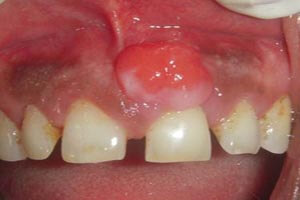

The pyogenic granuloma is a relatively common, tumorlike, exuberant tissue response to localized irritation or trauma. The name pyogenic granuloma is a misnomer since the condition is not associated with pus and does not represent a granuloma histologically. It is a reactive inflammatory process filled with proliferating vascular channels, immature fibroblastic connective tissue, and scattered inflammatory cells. The surface usually is ulcerated, and the lesion exhibits a lobular architecture.

Before